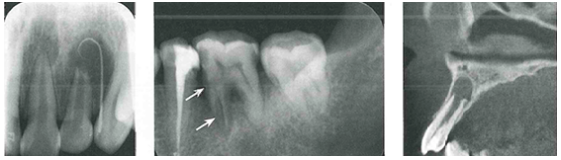

【影像学表现】患牙髓腔扩大,呈圆形或卵圆形或不规则形密度减低的透射影。发生于根管者,有长短不一、粗细不均沿根管的扩大影,髓室壁或根管壁变薄。可伴有根尖吸收和根尖感染,甚至发生折断。